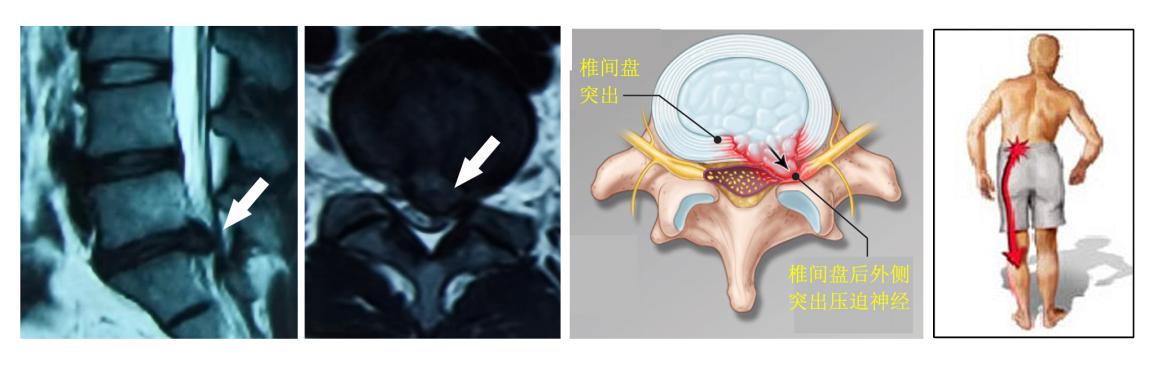

(2)椎间盘突出也可引起腰痛。突出的椎间盘会压迫由椎间孔内发出的神经根,导致大腿后外侧产生放射性疼痛,直到小腿、甚至到脚,有时会出现腿部刺痛而使不上劲儿。腿部疼痛通常比腰背部疼痛更严重,弯腰和坐立会导致疼痛加重,走路和躺着通常可缓解疼痛。